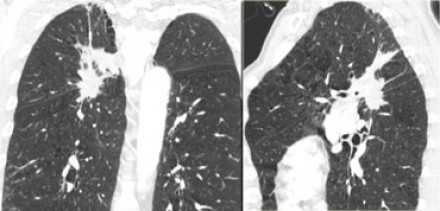

![]()

- Т1 - опухоль достигает 30 мм в диаметре или меньше в наибольшем измерении, окружена легочной паренхимой или висцеральной плеврой, нет признаков инвазии проксимальнее долевого бронха при бронхоскопии (опухоль не локализуется в главном бронхе)

- Т1(mi) минимально инвазивная аденокарцинома

- T1а - опухоль 10 мм в диаметре или менее в наибольшем измерении

- T1b - опухоль от 10 до 20 мм в диаметре в наибольшем измерении

- Т1с - опухоль от 20 до 30 мм в диаметре в наибольшем измерении